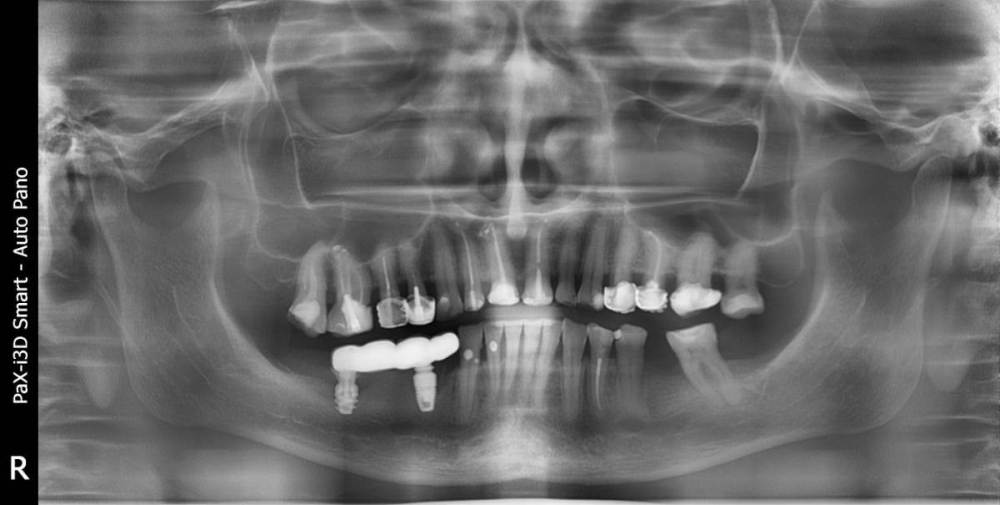

Вот с такой ситуацией обратилась к врачу, болел зуб мудрости.  Далее был сделан снимок (прилагаю фото решений- удаление опорных зубов с последующей заменой имплантами). PX20171201_162103_0000_000000FF.thumb.jpg.8c974cf49da3bb77db059abb91c7264c.jpg2018-01-24_013834.thumb.jpg.48a661d2a2f2d78a18d7b2906252d0a3.jpg2018-01-24_014845.thumb.jpg.0665ffa758959ace3ce9d7a8ff27421f.jpgпосле проведенных манипуляции появилась парастезия тройничного нерва, считаю это последствиями неверно установленного импланта, справедливо ли мое мнение?  Прохожу длительное лечение у невропатолога.  На крайнем визите врач отказал в помощи с этой проблемой и с обнаженным имплантом. (Прикладываю фото) 786267296_09_12_21.thumb.jpg.f332c30c240cb1ba19d2341b4f6014f1.jpg20220116_233530.thumb.jpg.c9cc82f18d25e9a905a2b7b1dc13eb8c.jpg20220116_232905.thumb.jpg.c3953c0b472c6e3ce1f46272ef507d2e.jpg1915694342_WhatsAppImage2022-08-20at19_39_20.thumb.jpeg.2099829af18d4d8c448126d5f323605f.jpegУ меня следующий вопрос:  верно ли назначенное лечение и насколько корректно установлены импланты, а также имелись ли противопоказания для установки имплантов, имея ввиду, что была убыль кости? Можно ли устанавливать импланты в таком случае?  прикладываю фото уже удаленного установленного на на импланты моста, правильно ли выполнен технически? (импланты пришлось удалить, а мост снять, чтобы сделать операцию по восстановлению кости, но уже в другой клинике. так как, как я писала выше, врач, установивший импланты отказал в помощи).

План лечения в виде удаления зубов и установки имплантов был назначен вам верно. Вариант с увеличением костной ткани и последующей имплантацией предпочтительней,чем ставить импланты без костной пластики. Но вариант,который делал первый доктор тоже не запрещен,видимо что то пошло не так